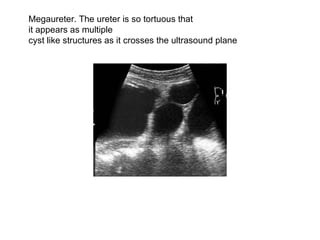

Megaureter. The ureter is so tortuous that it appears as multiple  cyst like structures as it crosses the ultrasound plane